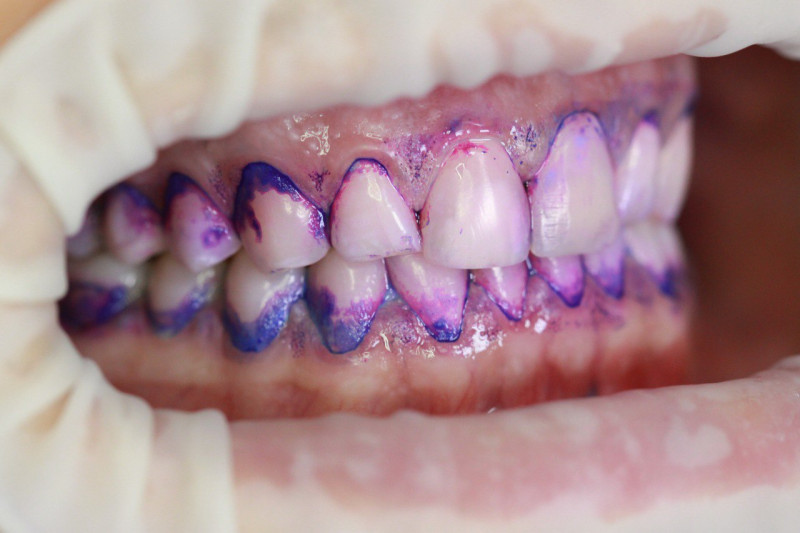

Index Dual работает по принципу селективного окрашивания: свежий налёт (до 24 часов) становится розовым, а зрелый кариесогенный налёт (более 24 часов) — синим.

• Для гигиенистов (Протокол GBT): Это базовый этап перед использованием Air-Flow. Окрашивание позволяет работать целенаправленно, экономя порошок и время врача.

• Для пародонтологов: Чёткая дифференциация старого налёта (синий цвет) указывает на зоны риска развития пародонтита и локализацию патогенной флоры.

Высокая контрастность Хорошо видно даже в пришейной зоне